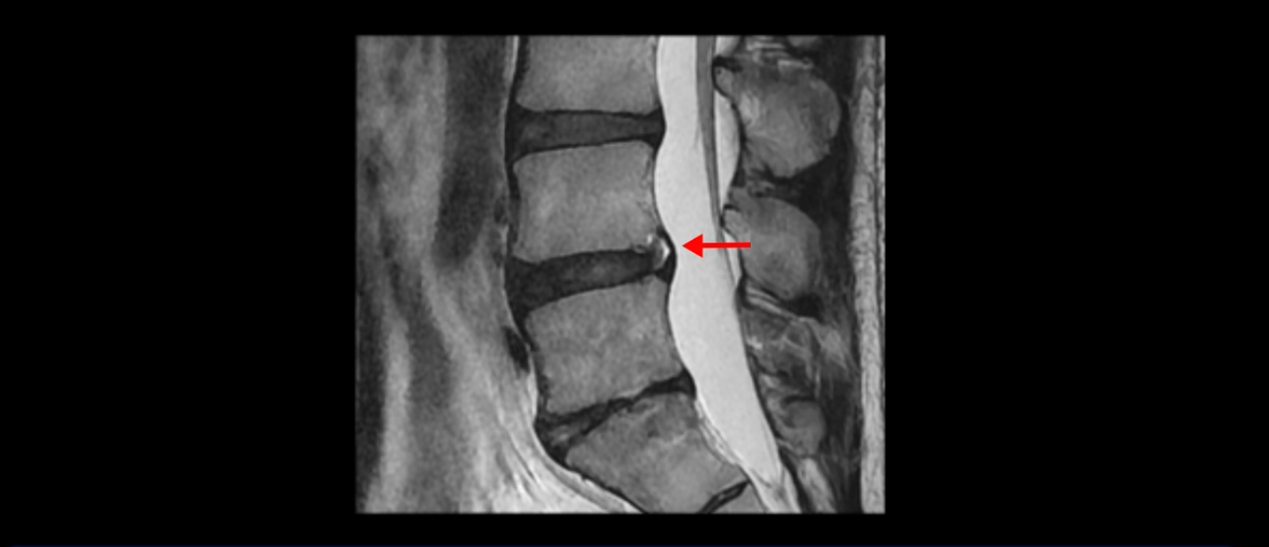

그런데 이분의 증상과 MRI가 전혀 일치하지 않는데, 왜 그런지 지금부터 자세히 설명드립니다. 이분 증상은 앉으면 엉치와 허리가 심하게 아파 10분 이상 앉는 게 어렵고 양쪽 발가락이 앉아있을 때나 누워있을 때 다 저립니다. 걸을 때도 아파서 10분 걷기도 어렵습니다. MRI를 마디마디 살펴보면 1번 2번은 오른쪽으로 살짝 밀려나온 디스크가 있지만 전혀 심하지 않고, 뒤에 또 설명하겠지만 최근에 밀려나온 급성 디스크가 아니고 오래된 디스크로 판단됩니다.

4번 5번은 가운데로 섬유륜이 찢어져서 디스크가 살짝 밀려나와 있지만 역시나 최근에 찢어지고 밀려나온 걸로 판단되지 않고 오래 전에 찢어진 흔적으로 보입니다.

5번 1번 역시 가운데로 디스크 조금 밀려 나와있지만 신경 공간 넓이는 아주 넓어서 신경 눌림 있을 거라고 예상이 안됩니다.

앞서 1번 2번, 4번 5번, 5번 1번의 디스크가 찢어지고 조금 밀려 나온 게 최근에 찢어진 게 아니고 오래된 걸로 보인다고 말씀 드렸죠. 왜 그럴까요? 만약 급성으로 찢어진 것이라면 아주 심한 디스크성 통증이 있겠죠. 기침이나 재채기를 하면 심하게 아프고 허리를 조금만 구부리거나 비틀면 아주 날카로운 통증들이 생길 겁니다. 그런데 이분은 이런 증상이 전혀 아닙니다. 또 디스크의 밀려나온 정도도 전혀 심하지 않기 때문에 이분이 가지고 계신 양쪽 다리 저림, 특히 이분은 누워있을 때도 양쪽 발이 발가락까지 쑤신다고 하는데 이정도 디스크 때문에 그런 증상은 생길 수가 없는 겁니다. 이처럼 이분의 가벼운 디스크 탈출은 이미 오래 전에 진행되었고 섬유륜 자체는 이미 아문 상태인데도 디스크내장증을 진단받은 환자들 중에는 본인이 섬유륜 파열 환자라고 끝까지 믿는 분들이 많습니다. 다시 말하지만 디스크내장증이라는 진단을 받은 환자들을 보면 거의 전부 다 섬유륜 파열 증상이 아닙니다. 증상이 완전히 다릅니다. 진단이 애초에 잘못되면 어떤 치료를 받아도 좋아질 수 없습니다.

이분은 어떤 한 병원에서 디스크 내장증 얘기를 들으셨는데요. 여기 보시는 것처럼 4번 5번의 하얀 HIZ(High Intensity Zone)을 보고 디스크 내장증의 근거로 얘기하는 병원들이 있는데,

이 HIZ는 섬유륜이 찢어졌다가 이미 아문 뒤에도 얼마든지 보일 수 있는 흔적일 가능성이 있어서 재채기를 하면 아픈지, 허리를 구부릴 때 날카로운 통증이 생기는가 등의 증상으로 구별해야 하는데 MRI만 보고 HIZ가 보이면 그게 마치 통증의 원인인 것처럼 얘기하는 의사들이 있습니다. 이분 MRI를 자세히 보고 증상을 정말 자세히 들어본 의사가 있었더라면 다른 환자분들처럼 증상과 MRI가 일치하지 않는다는 얘기를 들을 수 있었을 텐데 이분은 그런 얘기는 듣지 못했습니다.